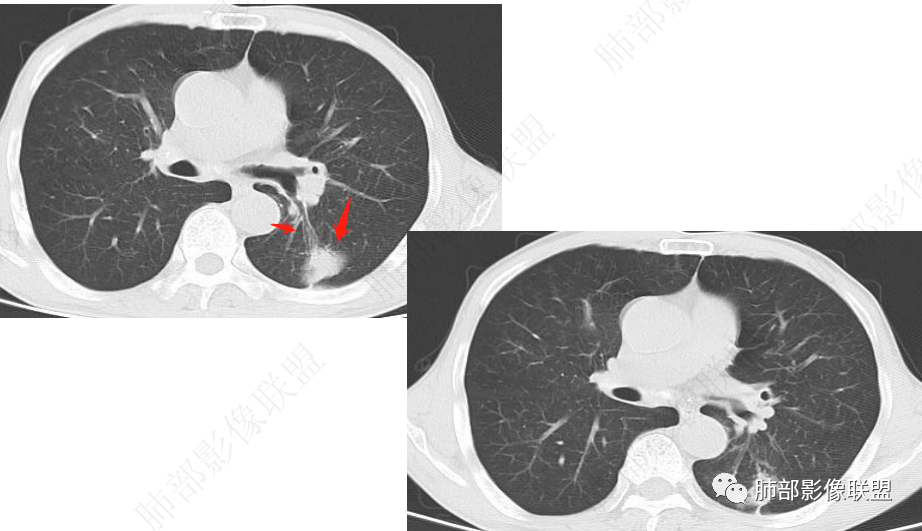

左肺及右肺中叶可见多发斑片状,条索及结节状高密度影,界不清,树芽征(+),中叶伴有支气管扩张,左肺下叶背段结节,周围伴毛刺,近端气管截断,实质密度不均匀,强化方式(看不清),8L,7及4区及左肺门见多发肿大淋巴结,老年男性,感染指标升高,呼吸道慢性病史,二元论,结核+左肺下叶背段恶性结节(鳞癌?)左肺下叶后基底段有新发感染?

双肺上叶斑点索条影,边缘清晰,可见树芽征。右肺中叶、左肺下叶局限性支气管扩张及索条影。左肺下叶背段结节膨胀感不强,直边,不均匀强化。左侧膈肌抬高相近肺内条片状影。纵隔及左肺门淋巴结稍增大。一元:先考虑感染性病变,NTM,努卡。两元:左下肺腺癌+淋巴结转移+膈神经麻痹。

老年男性,慢性咳嗽咳痰2年,加重10 天,左肺下叶实性结节影,边缘收缩平直,支气管进入后截断,周围有树芽征及结节影,周围支气管壁增厚狭窄,右肺中叶斑片影,左肺下叶条索影,考虑肉芽肿性炎,肺结核,NTM,考虑肺结核可能性大。鉴别NTM,炎性假瘤等。

左肺下叶不规则实性结节,无毛刺,支气管进入阻塞,周围树芽,远端长索条,左侧胸膜增厚,左肺门淋巴结略增大,右肺中叶支气管扩张,考虑炎性肉芽肿,结核、NTM,鉴别腺癌

左肺下叶不规则软组织密度影,密度不均,胸膜牵拉,环形强化,周围可见多发结节影,左侧肺体积略缩小,左肺上叶多发结节及条索,考虑结核,鉴别腺癌

左肺下叶不规则实性结节,密度不均,支气管进入阻塞,树芽,长索条,边缘强化,考虑炎性肉芽肿,结核、NTM。

慢性病史,急性起病,炎性标志物升高,左肺胸膜下结块,边界似清非清,可见晕中软毛刺,邻近肺野见斑点状卫星灶,可见近端支气管充气征,引流支气管管壁增厚,结块局部边缘平直,可见反晕征,综和分析考虑炎性肉芽肿性病变,尽管隐球夾膜试验阴性,但影像上还是首选隐球或TB,其次粘液腺癌

男,67,咳嗽、咳痰2年,加重10天。胸部CT:左肺下叶实性结节,边缘短毛刺、平直膨隆都有,近端支气管截断,胸膜牵拉,强化不均匀,纵隔、左肺门多发肿大淋巴结。左下叶远端尚可见树芽,胸膜下索条。考虑Ca,鳞?腺?鉴别TB、炎性结节。

整体体积缩小,附近多发索条、斑点状高密度影,继发性结核肯定有,倾向于陈旧性,问题是:是否有继发的恶性肿瘤?薄层看看边缘是否毛刺?

南边:是否边界清楚GGO?